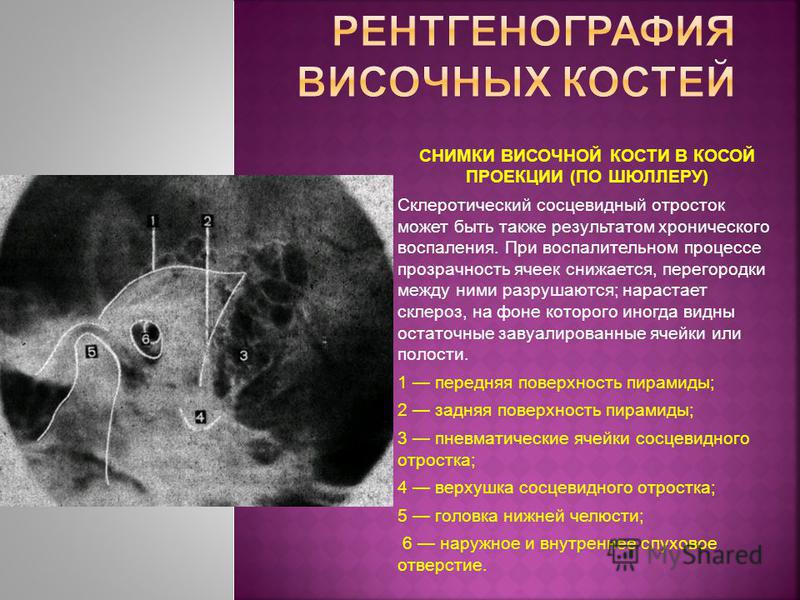

КТ анатомия сосцевидного отростка: особенности и показания